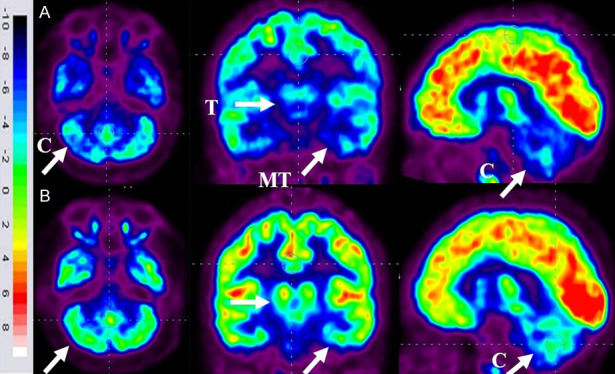

86名患者的家長同意在干預(yù)6個月后重復(fù)進行FDG-PET CT掃描以進行比較分析。干預(yù)前,這些患者的FDG-PET/CT掃描顯示雙側(cè)內(nèi)側(cè)顳葉皮層、丘腦和小腦的代謝活動降低[代謝減退]。此外,它們還表現(xiàn)出尾狀頭、殼核、眶額皮質(zhì)和前額葉皮質(zhì)的代謝活動增加(代謝亢進)。

干細胞移植六個月后,所有患者的大腦活動均得到改善。此前,代謝低下區(qū)域[內(nèi)側(cè)顳葉皮質(zhì)、丘腦和小腦]顯示FDG攝取增加,而代謝亢進區(qū)域[尾狀頭、殼核、眶額皮質(zhì)和前額葉皮質(zhì)]顯示FDG攝取減少(圖6)。在進行T檢驗時,發(fā)現(xiàn)干預(yù)前后這些區(qū)域的平均SUV出現(xiàn)了統(tǒng)計學(xué)上的顯著變化[P<0.05]。

A.頂行:標(biāo)有箭頭的藍色區(qū)域表明代謝低下。B. 下排:用箭頭標(biāo)記的綠色區(qū)域表明細胞移植后新陳代謝得到改善。

FDG PET CT大腦掃描被用作接受多劑量細胞移植的患者的額外結(jié)果測量。它用于監(jiān)測細胞水平干預(yù)的效果。這種功能性神經(jīng)影像技術(shù)利用18-FDG來研究大腦的代謝活動。我們對86名患者進行了FDG PET CT掃描腦部的比較研究,結(jié)果證明了其對新陳代謝的平衡作用。代謝低下的區(qū)域顯示代謝增加,而代謝亢進的區(qū)域顯示代謝減少。